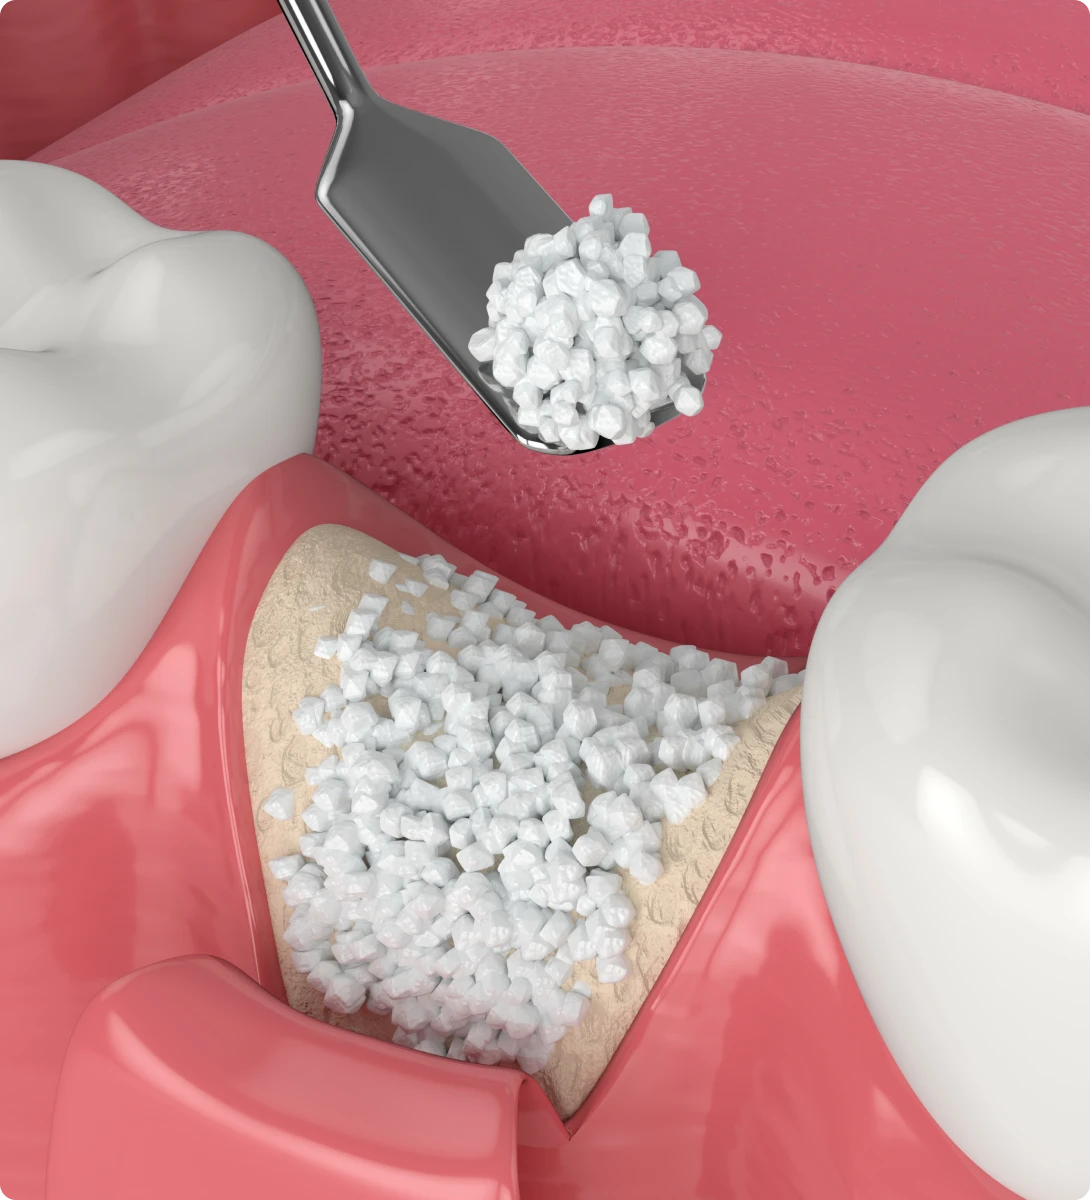

Greffe osseuse

La greffe osseuse augmente le volume d’os lorsqu’il est insuffisant pour poser un implant. Elle prépare la zone et renforce la structure du maxillaire ou de la mandibule